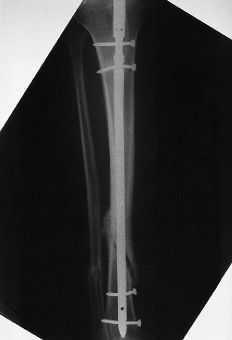

Para clasificar las fracturas se usó la clasificación para fracturas de la diáfisis tibial de Johner y Wruhs.11 Veintidós fracturas fueron Tipo A1, 15 fueron B1, ocho B3, 10 C1 y seis C3. Hubo 42 fracturas en hombres y 19 en mujeres, siendo la edad media de 42 años (mínimo: 17 y máximo: 87 años). La intervención se llevó a cabo una media de 26 horas (mínimo: 4 y máximo: 120 horas) tras el traumatismo. Se utilizó un clavo bloqueado intramedular AO/ASIF (Synthes) sin fresar para la tibia. Este clavo de acero tiene un diámetro de 8 ó 9 mm y se inserta sin fresar el canal medular. El diámetro del clavo que se utiliza se selecciona con la radiología preoperatoria. Se utilizó una mesa ortopédica e intensificador de imágenes para su introducción. No se usó manguito de isquemia. El enclavado se realizó a través de un abordaje transrotuliano, siendo el punto de entrada del clavo inmediatamente distal a la superficie articular proximal de la tibia, en la línea media y bajo la porción media del tendón rotuliano. El bloqueo proximal se realizó en todos los pacientes: 47 clavos fueron bloqueados con dos tornillos (uno dinámico y uno estático), ocho clavos con un tornillo dinámico, cinco con un tornillo estático y un clavo fue bloqueado con tres tornillos (dos tornillos estáticos y uno dinámico). Todas las fracturas fueron bloqueadas distalmente para el control axial y rotacional de la fracturas usando una técnica de manos libres (55 fueron bloqueadas con dos tornillos y seis con un tornillo). Postoperatoriamente se aplicó un vendaje de yeso corto y no se permitió cargar hasta la dinamización de la fractura. La dinamización se efectuó en 50 pacientes retirando el tornillo estático proximal. Once pacientes no necesitaron dinamización, ocho de ellos porque sólo tenían un tornillo de bloqueo proximal y tres porque cargaron sin permiso y el tornillo estático proximal se rompió. Los pacientes fueron seguidos hasta la consolidación de las fracturas y la retirada del material. El seguimiento medio fue 13 meses (mínimo: 12 y máximo: 20 meses).

El tiempo medio operatorio fue de 63 minutos (mínimo: 45 y máximo: 90 minutos). Se utilizó un clavo de 8 mm en 29 casos y de 9 mm en 32; se produjo una fractura intraoperatoria de la cortical posterior (Fig. 1). La dinamización se llevó a cabo en una media de 9 semanas (mínimo: 5 y máximo: 20 semanas). La carga completa postoperatoria se inició a una media de 8 semanas (mínimo: 1 y máximo: 19 semanas) tras la intervención. Catorce (6,2%) de los 226 tornillos empleados se doblaron o rompieron (tres tornillos estáticos proximales, uno dinámico proximal y 10 tornillos distales). En tres pacientes el clavo no fue dinamizado antes de cargar peso. En uno de ellos se rompieron todos los tornillos y en dos se rompió el estático proximal y los dos distales (Fig. 2). En tres pacientes se rompieron los tornillos distales a pesar de que el clavo había sido dinamizado.

Cincuenta y ocho fracturas (95%) consolidaron en una media de 20 semanas (mínimo: 11 y máximo: 24 semanas). Hubo dos casos de retardo de consolidación que finalmente consolidaron en 31 y 33 semanas y uno de pseudoartrosis que ocurrió en una fractura Tipo B3 que se dinamizó 19 semanas tras el enclavado. Este paciente fue tratado mediante injerto óseo y enclavado fresado. Hubo una relación estadísticamente significativa (p < 0,01) entre la dinamización temprana (entre las 4 y 8 semanas tras el enclavado) y la consolidación precoz (12-16 semanas tras en enclavado).

Se puede concluir que el enclavado intramedular bloqueado sin fresar es un tratamiento efectivo para las fracturas cerradas de la diáfisis tibial, con una alta tasa de consolidación y con pocas complicaciones, recomendando el clavo de 9 mm siempre que sea posible. La dinamización debe realizarse entre las 4 y las 8 semanas tras el enclavado. Retrasar la carga hasta que el clavo se ha dinamizado puede evitar la rotura de tornillos de bloqueo.